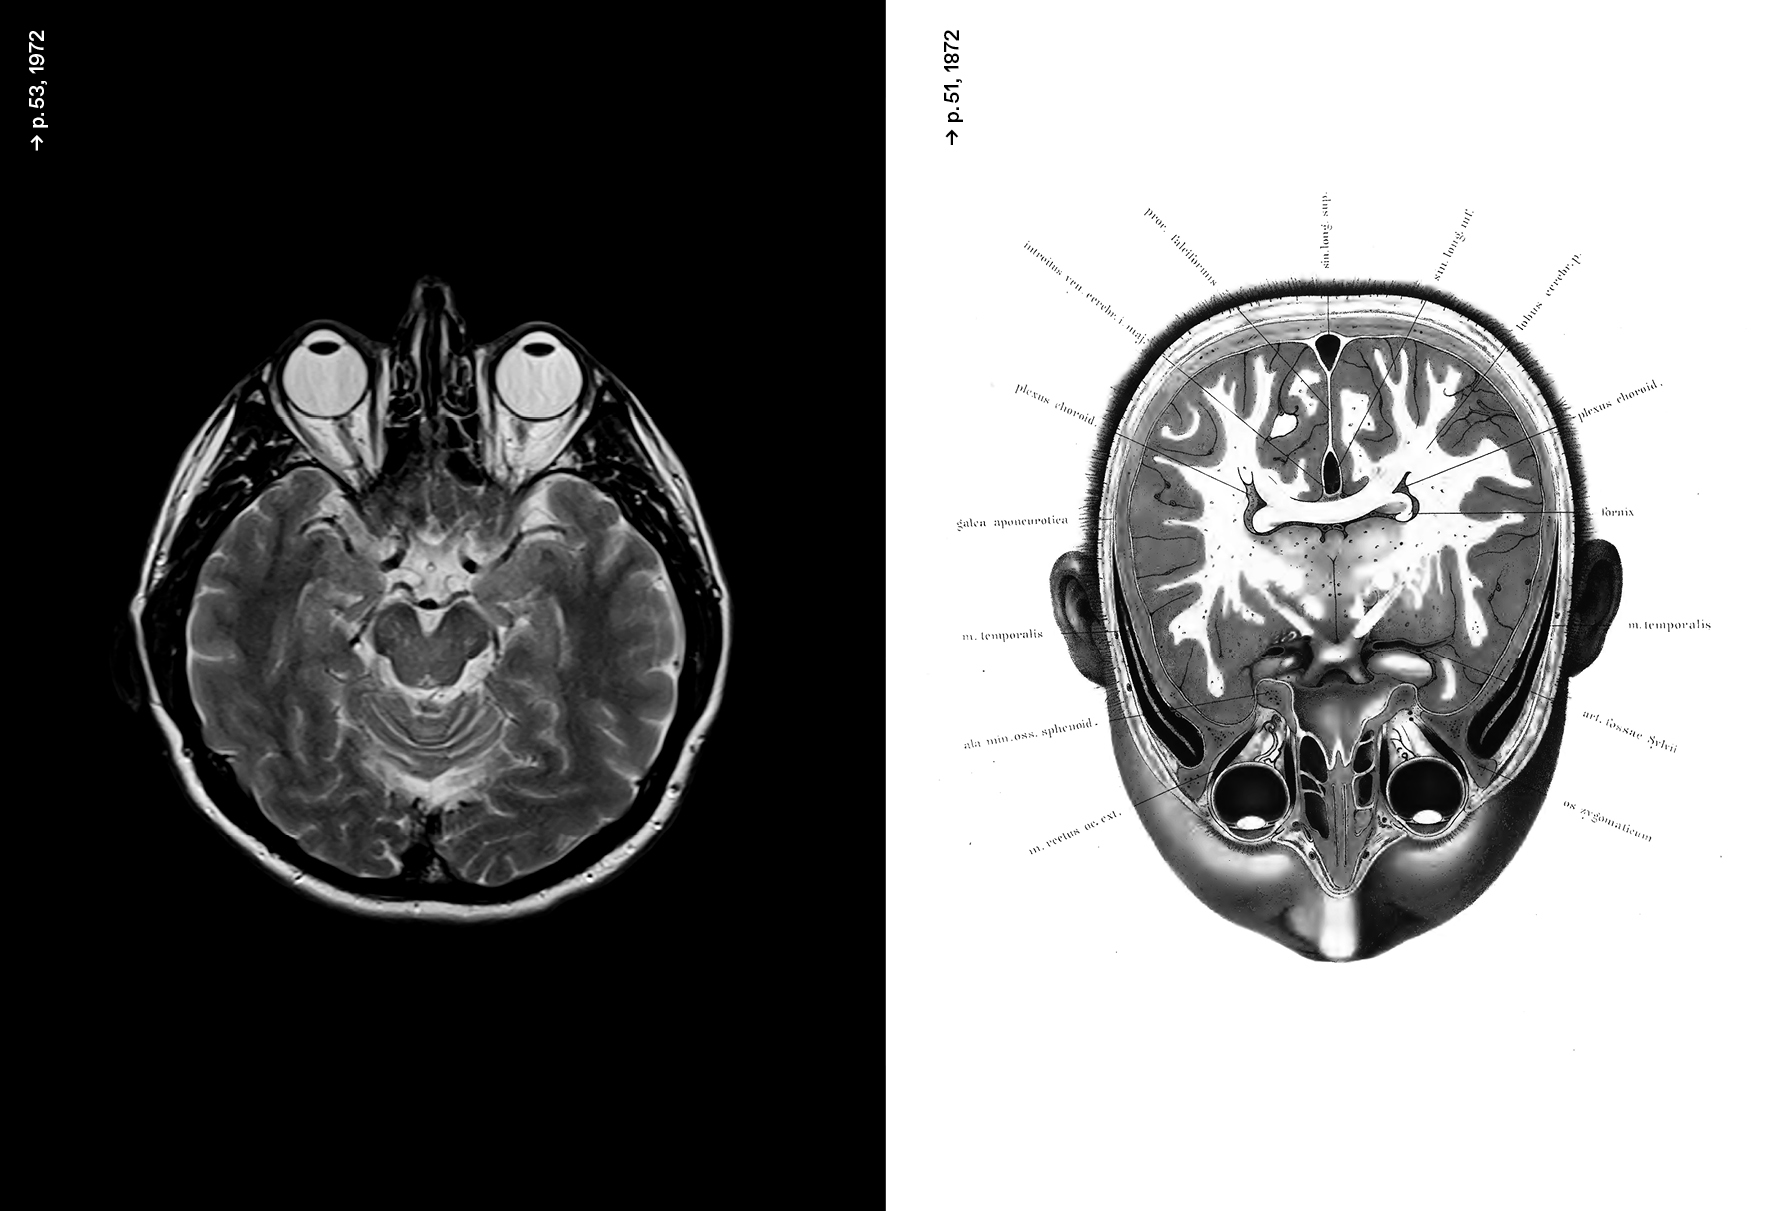

Les notions de « deep learning », de « machine learning » définissent aujourd’hui l’intelligence artificielle (IA) comme un nouveau paradigme établi aussi bien dans le domaine industriel, économique, militaire ou sociopolitique, que dans nos vies quotidiennes. Pourtant cette histoire n’a jamais été véritablement mise en relation avec celle des neurosciences et de la neuro-computation. « Objet cerveau », « Intelligence des jeux », « Cyber-zoo », « Extended Minds », « Deep Learning - Arbres et réseaux neuronaux »... La redéfinition des notions liées à l'IA nous permet de mieux comprendre le développement continu des recherches sur la simulation de l’intelligence humaine et son interaction permanente avec les domaines de la science et de la création.

Archéologies neuronales

Les différentes thématiques sont organisées autour de graphes. Les visualisations de données accompagnées d’essais proposent une lecture originale de l’IA. Ainsi, dans Corrélations, les intelligences simulées, Frédéric Migayrou nous présente l’histoire des recherches et des concepts qui déterminent aujourd’hui les enjeux de ces intelligences simulées. Un cerveau plastique de Camille Lenglois propose un panorama des créations contemporaines liées à ces thématiques. L'historien de l'art Pascal Rousseau avec Court-circuit, les neurones psychédéliques retrace les multiples expériences sensorielles du mouvement psychédélique. Les philosophes Pierre Cassou-Noguès (Pourquoi des tortues?) et Daniel Parrochia (Arboresences, graphes, réseaux, algorithmes) abordent les enjeux politiques et épistémologiques de l'IA.